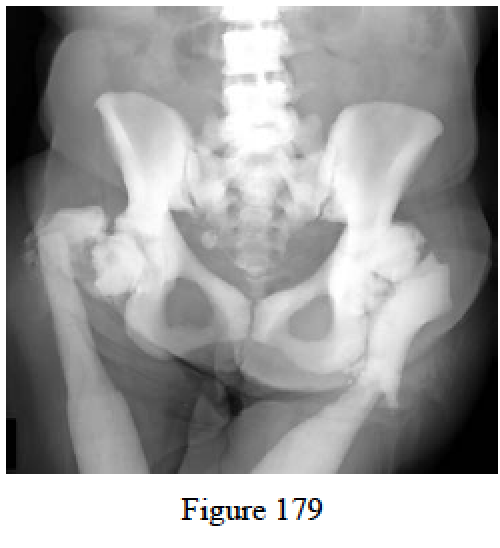

- Figure 179 is a recent pelvic radiograph of a 73-year-old woman who cannot ambulate. She developed blindness as an infant and has a history of difficulty with healing of limb fractures. What defect is associated with her disorder?

- PEX gene

- Fibrillin 1

- Collagen I

- Collagen oligomeric protein

- Carbonic anhydrase

- Carbonic anhydrase

RECOMMENDED READINGS

Dietz FR, Mathews KD. Update on the genetic bases of disorders with orthopaedic manifestations. J Bone Joint Surg Am. 1996 Oct;78(10):1583-98. Review. PubMed PMID: 8876589.

Einhorn TA. Metabolic bone disease. In: Einhorn TA, O’Keefe RJ, Buckwalter JA, eds. Orthopaedic Basic Science: Foundations of Clinical Practice. 3rd ed. Rosemont, IL: American Academy of Orthopaedic Surgeons; 2007:415-426.